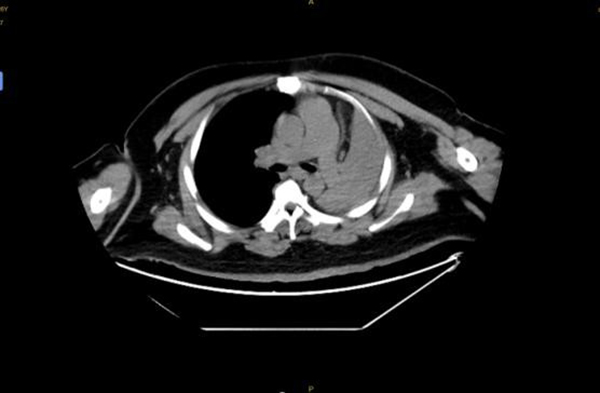

4月14日,王先生因“憋喘伴發(fā)熱咳嗽半月余”到徐州醫(yī)科大學(xué)附屬醫(yī)院急診就診。據(jù)王先生家人介紹,患者半個(gè)多月來,憋喘不斷加重,先后在徐州市多家醫(yī)院就診,考慮左肺不張伴感染,但通過積極抗感染治療,憋喘無改善并逐漸加重,同時(shí)出現(xiàn)發(fā)熱癥狀,體溫最高近39攝氏度。徐醫(yī)附院呼吸與危重癥醫(yī)學(xué)科何軍主任會(huì)診后,考慮患者智力異常,進(jìn)食方式特殊,不排除誤吸的情況,閱片后發(fā)現(xiàn)左主支氣管內(nèi)存在異物可能,需行氣管鏡檢查進(jìn)一步明確肺內(nèi)情況。考慮患者一般情況差,存在I型呼吸衰竭,肺部感染重等情況,于是將其收治在呼吸重癥監(jiān)護(hù)室(RICU)。

患者入院后進(jìn)行高流量氧療和抗感染治療,因?yàn)槠浞逝趾喜⒑粑ソ,肺部感染重,氣管鏡風(fēng)險(xiǎn)高,在與家屬充分溝通后,呼吸ICU團(tuán)隊(duì)于4月15日為王先生行床旁氣管鏡檢查,鏡下發(fā)現(xiàn)左主支氣管內(nèi)一白色圓形異物,表面為壞死覆蓋,清除壞死組織后,異物質(zhì)硬,表面光滑,無法鉗取。同時(shí)患者病情危重、麻醉評(píng)估風(fēng)險(xiǎn)極高,在陳碧主任的主持下,呼吸ICU團(tuán)隊(duì)經(jīng)過討論后決定行床旁氣管鏡取異物術(shù)。

季磊副主任醫(yī)師在楊翌、蔣宇及劉慧醫(yī)師的協(xié)助下,在全麻下經(jīng)氣管插管(8#)套管進(jìn)鏡,左主支氣管內(nèi)可見被粘痰、壞死物包裹一圓形異物,清理后發(fā)現(xiàn)異物為花生粒,長(zhǎng)徑約2cm,由于花生粒過大,無法通過8#氣管導(dǎo)管,于是將花生粒分解,通過使用圈套器、異物鉗以及網(wǎng)籃逐一將其取出,總共歷時(shí)1.5個(gè)小時(shí)。取出異物后,左主支氣管及其分支可見大量黃色膿性分泌物,予以充分吸除。